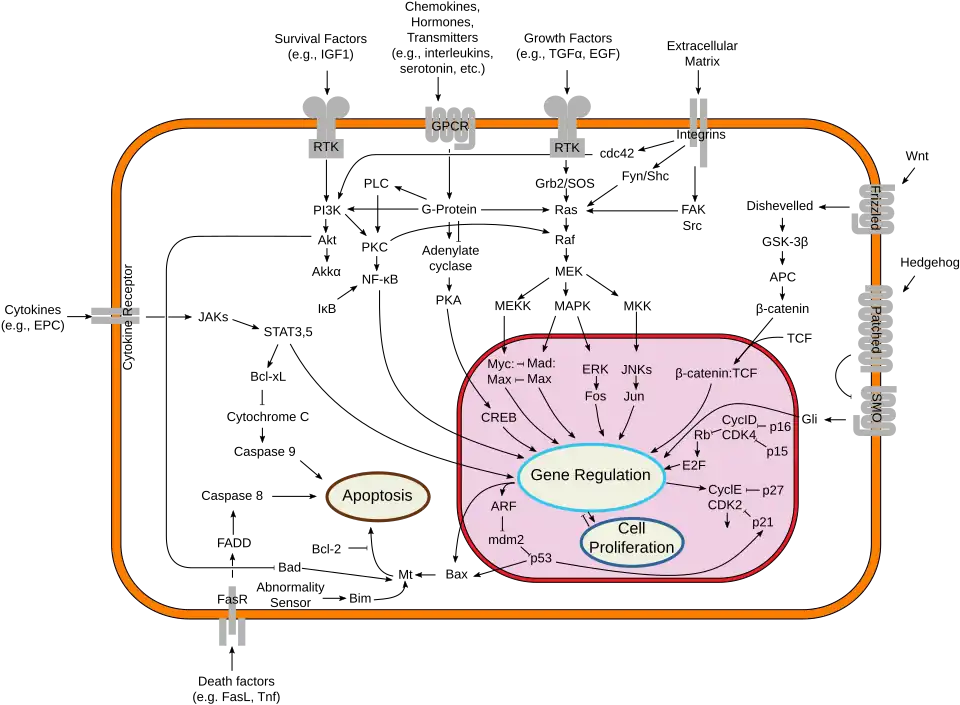

Breast cancer, like other cancers, occurs because of an interaction between an environmental (external) factor and a genetically susceptible host. Normal cells divide as many times as needed, and stop. They attach to other cells and stay in place in tissues. Cells become cancerous when they lose their ability to stop dividing, to attach to other cells, to stay where they belong, and to die at the proper time.

Normal cells will self-destruct (programmed cell death) when they are no longer needed. Until then, cells are protected from programmed death by several protein clusters and pathways. One of the protective pathways is the PI3K/AKT pathway; another is the RAS/MEK/ERK pathway. Sometimes the genes along these protective pathways are mutated in a way that turns them permanently "on", rendering the cell incapable of self-destructing when it is no longer needed. This is one of the steps that causes cancer in combination with other mutations. Normally, the PTEN protein turns off the PI3K/AKT pathway when the cell is ready for programmed cell death. In some breast cancers, the gene for the PTEN protein is mutated, so the PI3K/AKT pathway is stuck in the "on" position, and the cancer cell does not self-destruct.[129]

Mutations that can lead to breast cancer have been experimentally linked to estrogen exposure.[130] Additionally, G-protein coupled estrogen receptors have been associated with various cancers of the female reproductive system including breast cancer.[131]

Abnormal growth factor signaling in the interaction between stromal cells and epithelial cells can facilitate malignant cell growth.[132][133] In breast adipose tissue, overexpression of leptin leads to increased cell proliferation and cancer.[134]

Some mutations associated with cancer, such as p53, BRCA1 and BRCA2, occur in mechanisms to correct errors in DNA. The inherited mutation in BRCA1 or BRCA2 genes can interfere with repair of DNA crosslinks and double-strand breaks (known functions of the encoded protein).[135] These carcinogens cause DNA damage such as DNA crosslinks and double-strand breaks that often require repairs by pathways containing BRCA1 and BRCA2.[136][137]